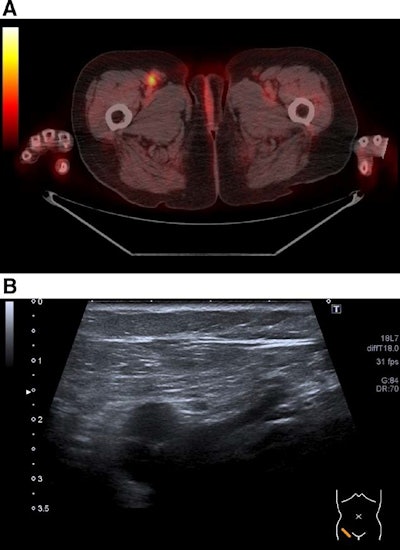

Overall, F-18 FDG-PET/CT identified 824 cancer lesions and ultrasound identified 726. On a per-exam basis, an analysis revealed significant differences for the sensitivity of F-18 FDG PET/CT (80%) compared to whole ultrasound (63%) and peripheral lymph node ultrasound (61%). PET/CT's specificity was slightly lower compared with ultrasound, however, at 96% versus 98% for whole ultrasound and 99% for abdominal ultrasound, the researchers reported.